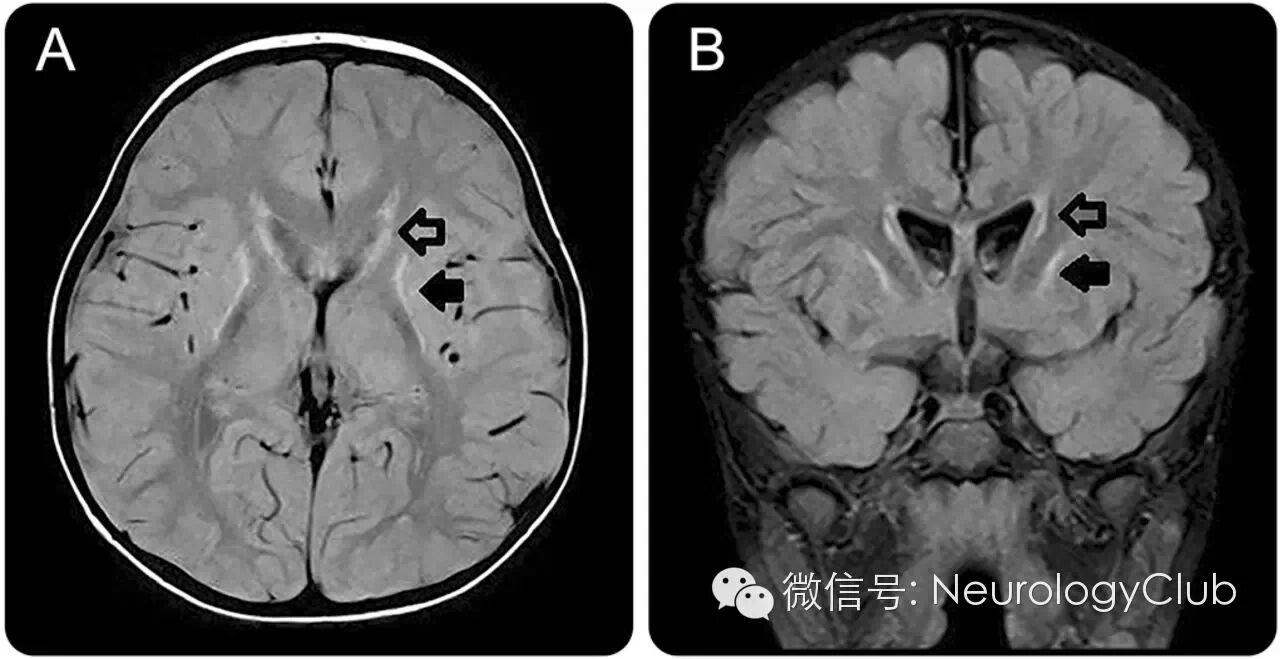

病例2

41岁患者,女性。

(T2/FLAIR提示双侧小脑深部白质[齿状核]及基底节区[苍白球]对称性高信号)